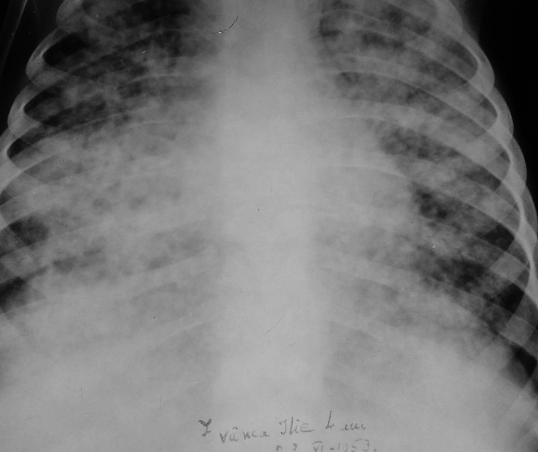

Rx toracică, incidență P-A

DESCRIERE:

DX: emfizem pulmonar

DD: